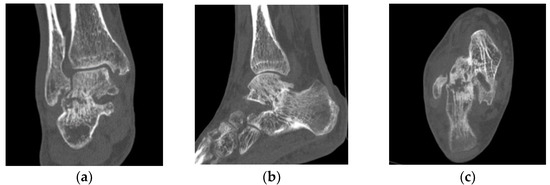

2. Case Presentation